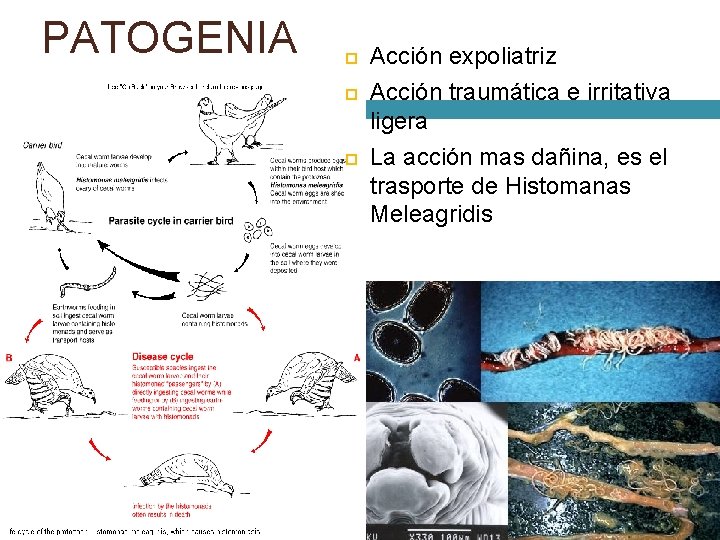

PATOGENIA Acción expoliatriz Acción traumática e irritativa ligera La acción mas dañina, es el trasporte de Histomanas Meleagridis